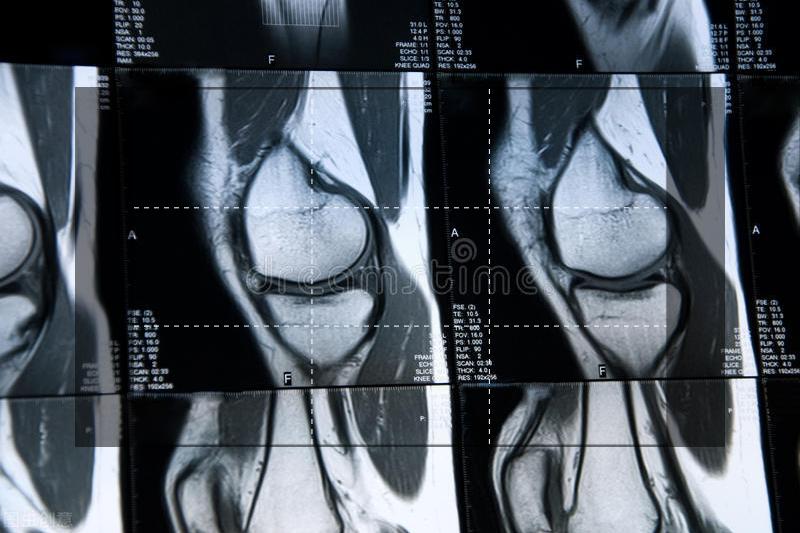

- 退变型,例如半月板的粘液变性、嗜酸性退变、疤痕、半月板钙化等,这种退变型的半月板在膝关节磁共振上能看到半月板内点状或者线状高信号,但是不达到关节面,一般来说是跟膝关节的退行性和骨关节炎变密切相关的,多发生在40岁以上。

关于半月板的损伤,需要从症状、查体、检查三个方面来全面评估,例如半月板在所有的磁共振片子上都呈现均匀的低信号,如果说在磁共振上看到半月板明显的二级信号,那么也不能轻易判断是退行性变或者外伤,如果病人年级较大,可以倾向于半月板退变引起的信号异常,但如果病人年龄仅有一二十岁,退变的可能行不大,这时候要倾向于考虑有无外伤。